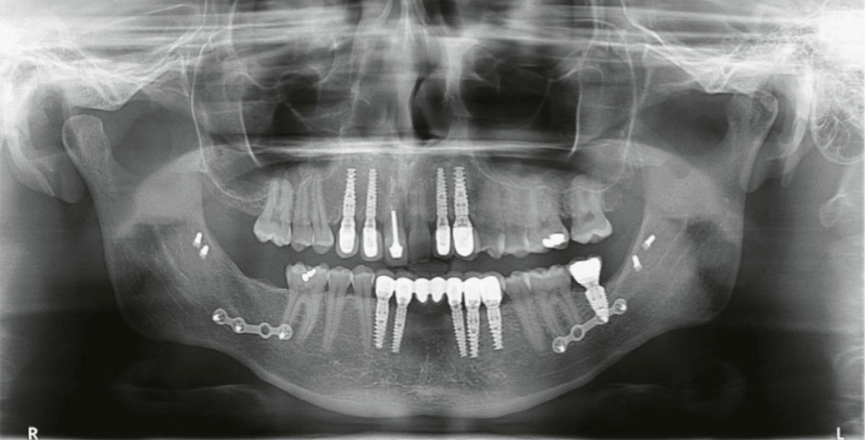

CT示OBG术前术后。图源自引文1

(CT示OBG修复后。图源自引文1)